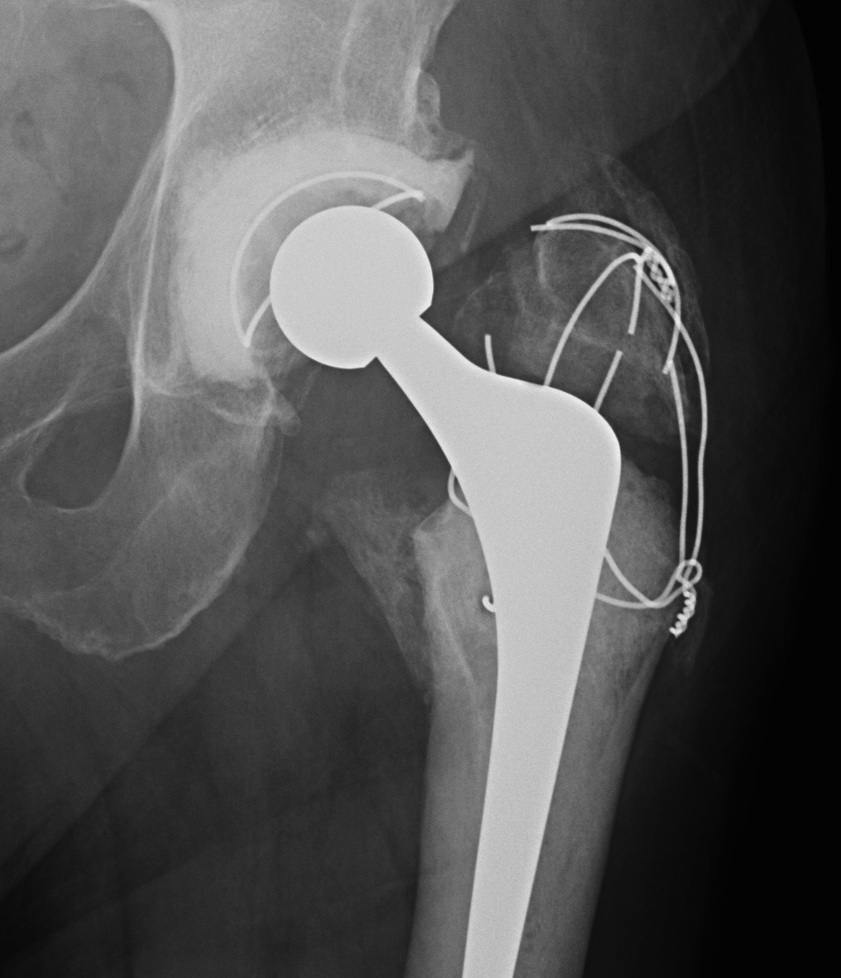

Trochanteric Slide

Concept

- PA osteotomy

- vastus lateralis and G medius left attached to fragment

- fragment retracted anteriorly

Fixation

- wires

- grip plate